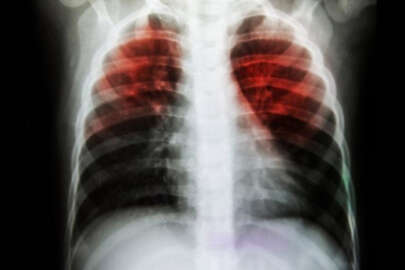

Verem, tedavi edilmezse öldürücü bir hastalık...

Verem, hava yoluyla, öksürmekle, hapşırmakla, konuşmakla bulaşan bir hastalık...

Ve verem, uzun süre havada canlı olarak asılı kalabilen mikropları soluduğumuz zaman önce akciğerlere, daha sonra kan yoluyla vücudun başka organlarına da yayılabilen bir hastalık...